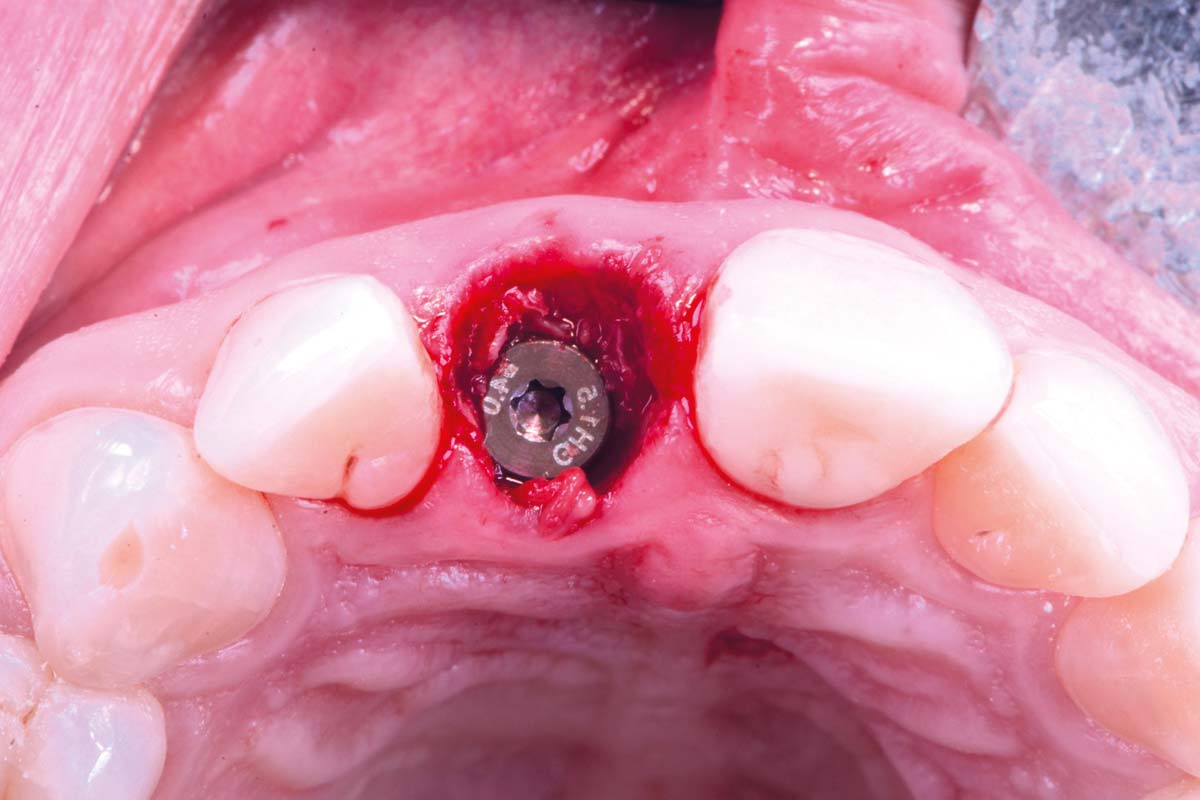

10/30 - Occlusal view – 4 mm placement depthExcellent aesthetic result of buccal augmentation with mucoderm® and maxgraft® after immediate implant placement - 3-years follow-up - Dr. A. Puišys